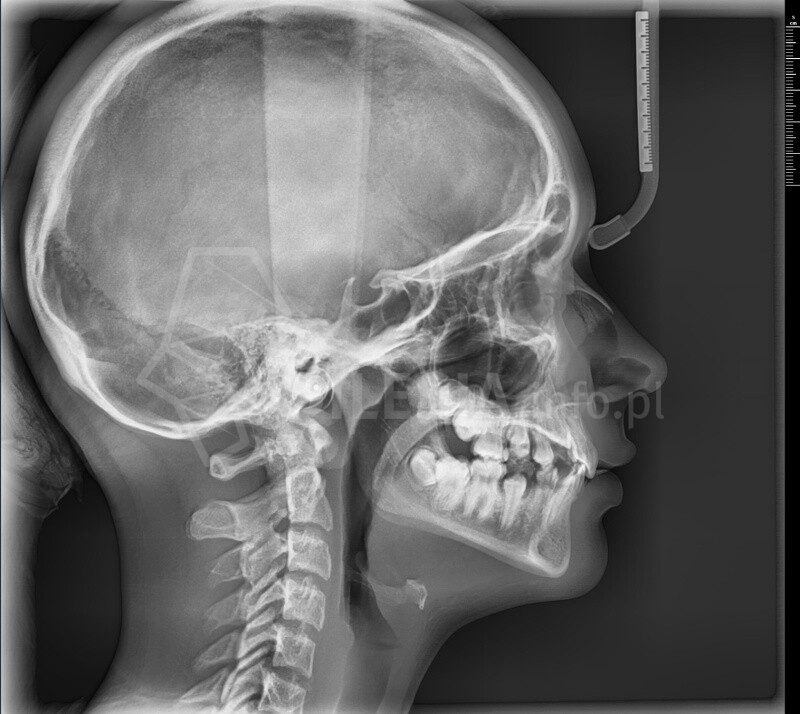

Pracownia wyposażona jest w tomograf stożkowy Vatech Green X (model 2025) – najnowszej generacji urządzenie, które łączy najwyższą jakość obrazów 2D i 3D z minimalną dawką promieniowania.

Skanowanie trwa zaledwie 2,9 sekundy, a technologia AI automatycznie redukuje zakłócenia i poprawia ostrość zdjęć.

CBCT (tomografia stożkowa) to nowoczesne badanie 3D, które pokazuje zęby, kości, zatoki i stawy skroniowo-żuchwowe w pełnym trójwymiarze. Umożliwia bardzo dokładne zaplanowanie leczenia chirurgicznego, ortodontycznego, implantologicznego i laryngologicznego.